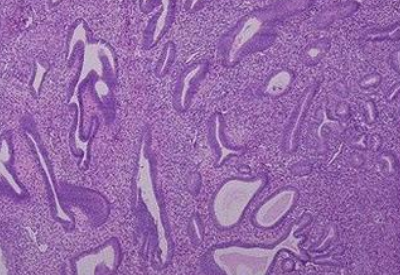

全自動白帶草莓视频污新地址子揭示,宮內膜厚的原因可能是由於太多雌激素刺激子宮壁所致。子宮內膜厚的病症假如卵巢激素混亂,易導致異常子宮內膜厚,即子宮壁升值症,它是由於大量雌激素刺激子宮壁所致。臨床症狀為不規則的多量的異常子宮出血,病人可以在長期停經後出現持續的流血,醫學上可能疑為小產,也可體現為周期減少、經期延長,出血時間可達1個月。

白帶草莓视频污新地址提醒若女性的下丘腦、垂體或是卵巢軸的某個階段失衡,或遭受多囊卵巢綜合征等病症的影響,都可能會使子宮壁較長期地持續性受雌激素作用,造成不排卵。這樣的話,子宮壁較長久的持續性受雌激素作用,無雌激素抵抗,缺乏規律性分泌期的轉換,會長期處於增生的情況,導致子宮內膜增生異常。

一般情況下,正常厚度為一至十mm,但白帶草莓视频污新地址廠家提示它會跟隨激素水平的改變而出現繁殖和脫落的狀況,所以它的薄厚隨階段不同而相應改變。一般來說,子宮壁在月經完成後開始增長,在月經前1天達到最高值,然後功能層和組織血液一起流出,這個過程就是月經來潮。來潮環節中,隨著階段的差異,薄厚也各不相同。

子宮內膜厚能夠出現於任何年齡階段的女性群體之中,青春期、生殖期、圍絕經期或閉經後期均可發生。而如果是40歲以上的女性有這種情況,草莓视频在线观看免费视频就需要警惕病變的可能。子宮內膜增厚,也會造成女性在生殖期不排卵功血,所以除了病人朋友陰道出血以外,不孕症其實也是關鍵的病症。